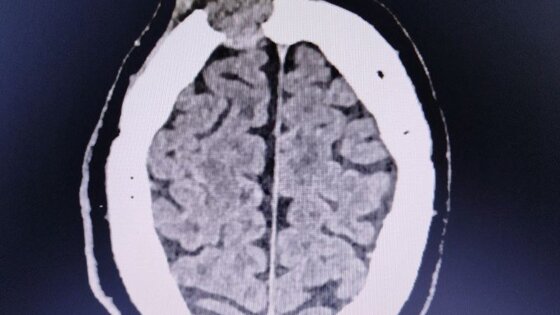

Ранее в ГКБ №7 обратился мужчина, который за три недели до этого ударился и на его лбу выросла шишка. За прошедшее время она не только не прошла, но и немного подросла. Компьютерная томография показала, что это опухоль, которая уже начала разрушать лобную кость. Пациента госпитализировали в нейрохирургическое отделение.

Случай оказался непростым: один край опухоли лежал над самой крупной веной мозга, а другой разрушал стенки лобных пазух. В результате образование создало сообщение между полостью черепа, полостью носа и внешней средой, а это опасно развитием гнойных осложнений.